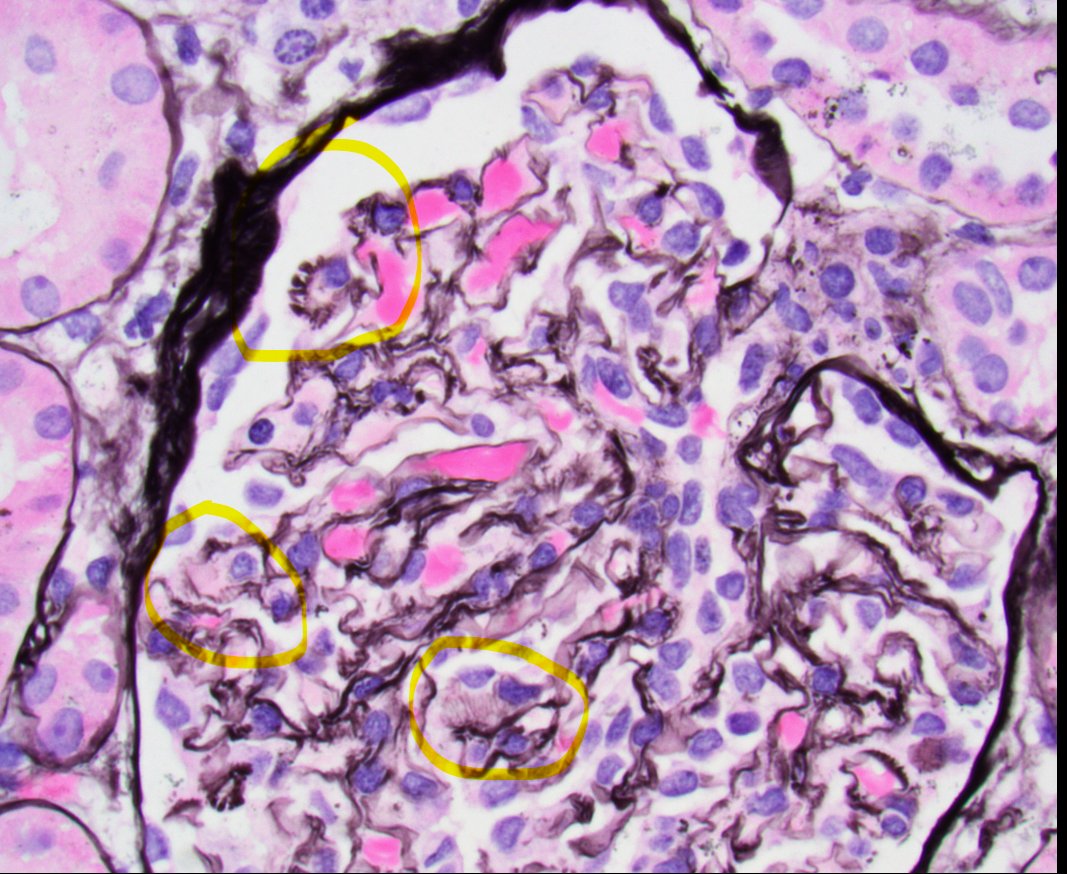

Disappearing glomeruli: loss of linear IgG in anti-GBM nephritis

In a patient with subnephrotic proteinuria, negative immunofluorescence, and segmental foot process effacement, what is your diagnosis? #DiagnoseThis #nephtwitter #pathtwitter #renal #kidneypath